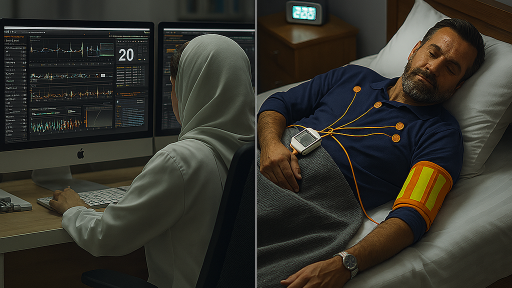

تشخیص ضربان نامنظم معمولاً با نوار قلب (ECG) آغاز میشود. اگر آریتمی گذرا باشد و در لحظه ثبت نشود، از هولتر ۲۴ تا ۷۲ ساعته یا مانیتورینگ طولانیمدت استفاده میشود. این روشها امکان ثبت ریتم قلب در شرایط واقعی زندگی را فراهم میکنند و برای تشخیص آریتمیهای پنهان بسیار ارزشمندند.

در برخی موارد، پزشک از اکوکاردیوگرافی برای بررسی ساختار قلب و عملکرد دریچهها استفاده میکند. اگر احتمال بیماری عروق کرونر وجود داشته باشد، تست ورزش یا CT آنژیو ممکن است لازم باشد. انتخاب تست مناسب به علائم و شرایط بیمار بستگی دارد.